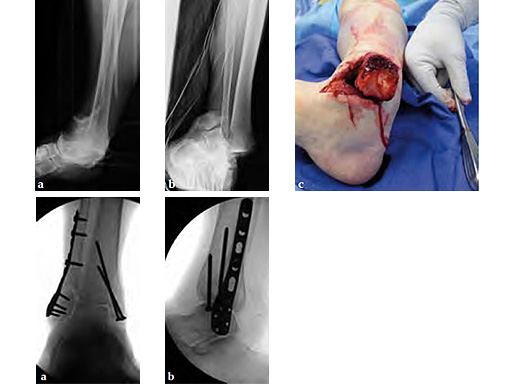

Case 1: 55-year-old male fell off a horse and sustained an open pronation abduction ankle fracture dislocation.